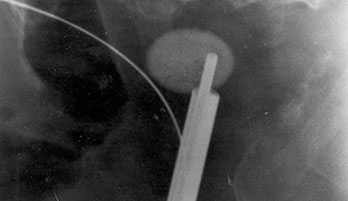

Urology_MEIn this medical segment we offers several laser systems and delivery devices that are considered for the standard care in urology. With an extensive product range for urologic laser applications – state-of-the-art laser systems, fibers, handpieces and other accessories you will be well equipped for the advanced treatment of BPH, stones, strictures and tumors. All fibers are free of latex and DEHP and delivered sterile for immediate use. Among other products, we provide also a morcellator with precise controlling over suction level and its speed, used for the removal of resected prostate tissue from the bladder.